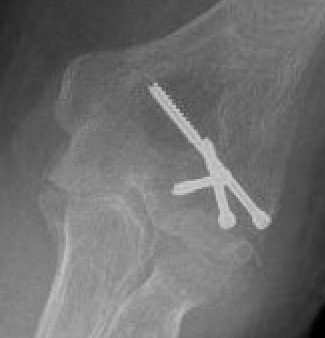

ORIF Type II with screws

ORIF with AP screws

Usually AP headless compression screws (violates articular surface)

- +/- PA screws (risk AVN)

AP v PA screws

Heller et al J Hand Surg Am 2025

- systematic review of AP v PA screws capitellum fixation

- higher AVN with PA screws (29% vs 11%)

- higher revision fixation with AP screws (7 v 3%)

- higher heterotopic ossification with AP screws (22 v 7%)